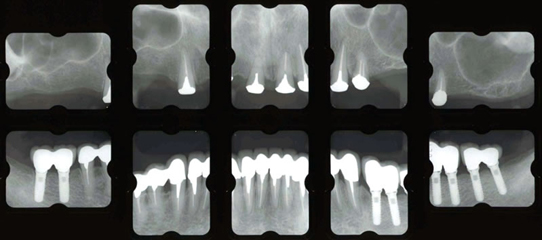

治療後

下顎の左右奥歯はインプラント治療により固定製に、弱っていた下の前歯はセラミック冠で固定しました。上顎は磁石義歯としました。しっかり咬む事ができました。